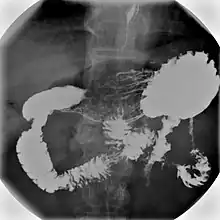

Barium meal examination showing the stomach and duodenum in double contrast technique with CO2 as negative contrast medium